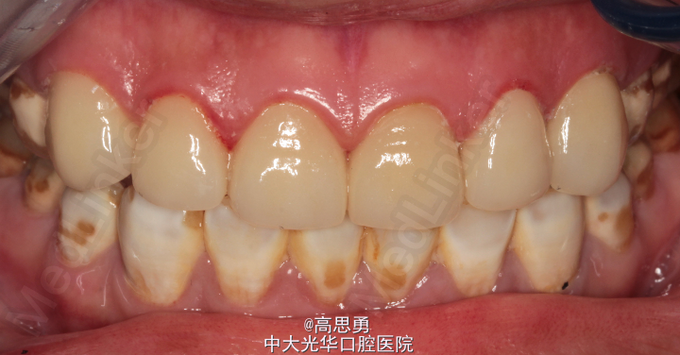

诊断:氟斑牙(着色型、中度) 患者意愿:患者希望尽快解决全口牙颜色改变的问题,不希望接受效果不明确、复诊次数多、维持时间短的治疗方案,可以接受费用较高的治疗方案,希望达到牙齿永久的形态、排列、颜色的尽可能完美的效果,但要求尽量少损伤牙体结构。下颌牙暂时不修复。 治疗方案:全瓷贴面修复,改善前牙美观。

个人觉得对于氟斑牙的颜色改变的治疗方法选择:1、贴面;2、beyond冷光美自;3、冠修复,其他通道还有什么建议吗?